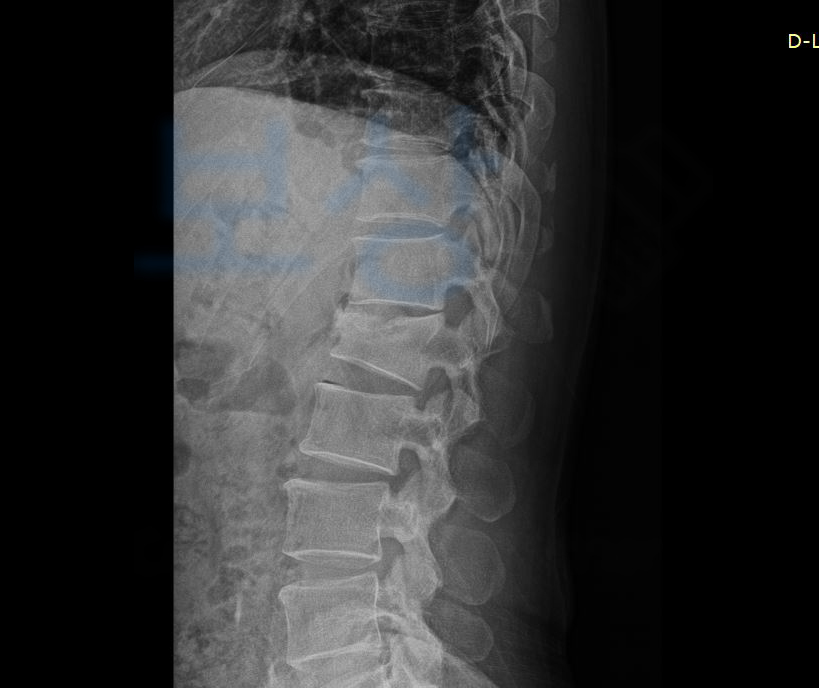

L1 부위의 골절 S3202 즉 요추1번 척추압박골절 진단을 받아 최소 12주간의 요양이 필요하셨는데요, 위 처럼 요추압박골절은 추락하거나 넘어지거나 부딪히는 외부의 강한 충격에 의해

척추에서도 움직임이 많은 요추와 흉추가 만나는 흉추12번이나 요추1번과 같은 부위에 흔히 발생합니다. 흉추와 요추가 만나는 부분은 흉추의 후만과 요추의 전만이 교차하기에 충격이 고스란히 집중되고 대부분 척추의 앞기둥 부위가 골절됩니다.